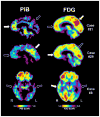

Methods: Twenty-eight patients with atypical dementia underwent positron emission tomography imaging with the amyloid imaging tracer Pittsburgh compound B (PiB). Twenty-six had [18F]fluoro-2-deoxy-D-glucose positron emission tomography scans. After extensive clinical evaluation, this group of patients generated considerable diagnostic uncertainty and received working diagnoses that included possible Alzheimer's disease (AD), focal dementias (e.g., posterior cortical atrophy [PCA]), or cases in which no clear diagnostic category could be determined (dementia of uncertain etiology). Patients were classified as PiB-positive, PiB-negative, or PiB-intermediate, based on objective criteria. Anterior-posterior and left-right indices of PiB and [18F]fluoro-2-deoxy-D-glucose uptake were calculated to examine differences in distribution of amyloid pathology and metabolic changes associated with clinical phenotype.

Results: Eleven patients (39%) were PiB positive, 16 were PiB negative (57%), and one (4%) was PiB intermediate. By diagnostic category, three of 10 patients (30%) with dementia of uncertain etiology, one of five (20%) with primary progressive aphasia, three of five (60%) with PCA, and four of seven (57%) with possible AD were PiB positive. Brain metabolism of both PiB-positive and PiB-negative patients was generally similar by phenotype, but appeared to differ from typical AD. PCA patients also appeared to differ in their relative distribution of PiB compared with typical AD, consistent with their atypical phenotype.

Conclusions: AD pathology is frequently present in atypical presentations of dementia and can be identified by amyloid imaging. Clinical phenotype is more related to the pattern of cerebral hypometabolism than the presence/absence of amyloid pathology. These findings have diagnostic, prognostic, and therapeutic implications.